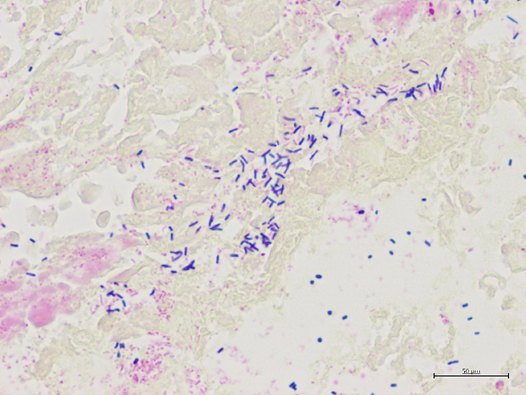

病変部ではグラム陽性大桿菌(かんきん_棒状・円筒状の細)が多数みられる

(強拡大、グラム染色)

■病変部では、グラム陽性大桿菌(かんきん_棒状・円筒状の細菌)が多数みられました

■小腸内容物から病原菌の分離を行ったところ、ヒトの食中毒の原因でもあるClostridium perfringen(クロストリジウム パーフリンジェンス) が分離されました

■これらの研究結果よりカラスの死因として一番多い出血性腸炎の原因はC.perfringensであることが明らかとなりました